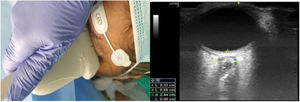

La exploración ecográfica se efectuó con el paciente en decúbito supino con cabeza en posición neutra (flexión de cuello y extensión de cabeza) y ojos cerrados. El operador se situaba a la cabecera del paciente. La sonda ecográfica se apoyaba con suavidad sobre el párpado superior, tras aplicar abundante gel ecogénico, en eje transverso del globo ocular, rotándola hasta encontrar la imagen del nervio óptico, tal como aparece en la figura 2. Se realizaba la medida del diámetro del nervio óptico a 3 mm posteriores a su entrada en el globo ocular.

Colocación de sonda lineal e imagen del globo ocular e imagen ecográfica del globo ocular. El estudio ecográfico se realizaba con aparato de ultrasonidos en modo-B, fijando unos parámetros de índice térmico menor de 1 e índice térmico menor de 0,2. El foco se situaba 1-2 cm por debajo del objetivo (origen del nervio óptico en el globo ocular).